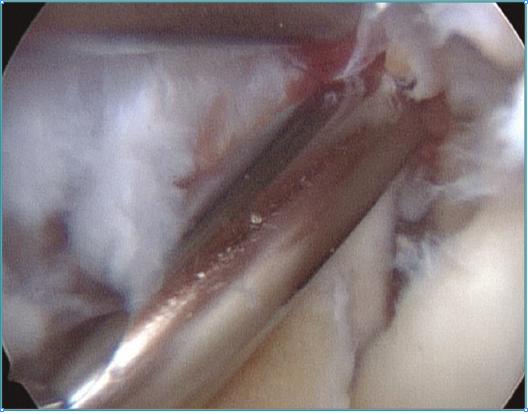

Figura 2. Visión artroscópica desde el portal anteromedial de un osteofito en la coronoides, disecado con un vaporizador de gancho, previamente a su resección con fresa motorizada.

Trabajaremos la parte ósea en primer lugar, resecando los osteofitos de la coronoides y de la fosa coronoidea, así como de la cabeza radial o de la articulación radiocubital si fuera necesario. Una vez hemos finalizado la parte ósea, procederemos realizar la capsulotomía anterior si está indicada.